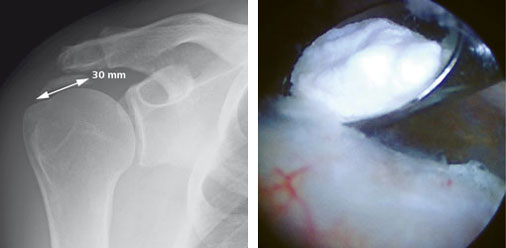

Links: Röntgenbild eines Kalkdepots (Durchmesser gekennzeichnet)

Rechts: Intraoperatives Bild. Während der Operation kann der Kalkherd mit speziellen Löffeln herausgeholt werden.